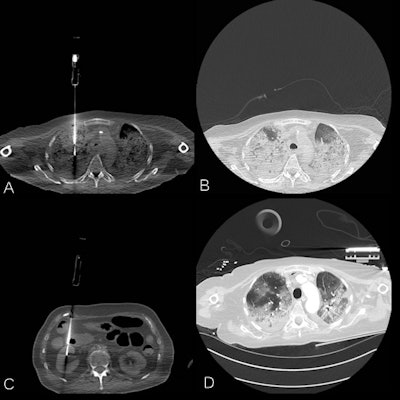

The autopsies include a comprehensive CT scan of major organs, starting with the patients' heads and ending just below their pelvis. Radiologist Dr. Jan Vanrusselt also takes needle biopsies from the lungs and other organs.

Patients with either severe acute respiratory syndrome coronavirus 2 (SARS-CoV-2) polymerase chain reaction (PCR) positivity or radiologically confirmed COVID-19 who died during hospitalization were included in the study after oral informed consent was obtained from the legal representative, Vanrusselt explained. A whole body CT-scan was performed, followed by CT-guided needle biopsies. Four sterile lung biopsies were taken for microbiology examination and at least two biopsies from heart, lungs, liver, spleen, kidneys, and abdominal fat for histological examination. Additional samples were taken when indicated.